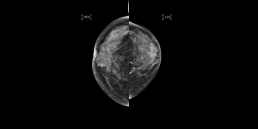

Femme de 77 ans avec des antécédents de cancer du sein à gauche, traité par tumorectomie gauche et radiothérapie en 1994.

La mammographie objective une surdensité supéro-externe du sein droit marquée 5 au score MammoScreen™.

Pas d’autre lésion intra-mammaire notable à droite comme à gauche.

Cette surdensité mammographique correspond en échographie à un nodule de 7 mm atténuant de type ACR 5 dont la biopsie confirme un carcinome canalaire infiltrant de grade 1.

MammoScreen™ a aidé à la détection précoce d’une surdensité dans une glande mammaire hétérogène, chez une patiente déjà traitée d’un cancer controlatéral.